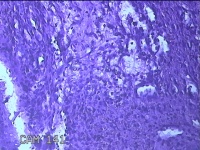

右下唇肿物

性别

女

年龄

12岁

临床诊断

唇囊肿

一般病史

右下唇部肿物一月余。

标本名称

大体所见

灰白粉红色肿物0.8x0.7x0.2cm一个,表面光滑。

图1